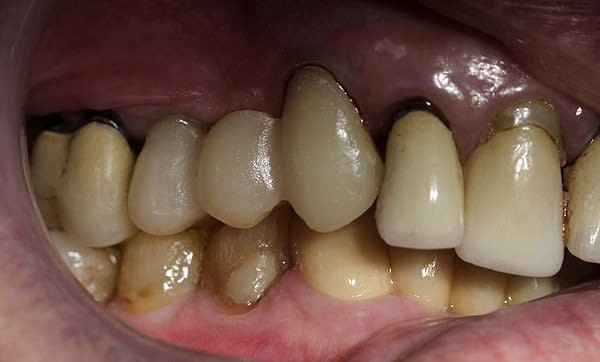

Voici les photos du premier cas, les embrasures ont été renforcées au maximum car la DV est très réduite, j'ai préféré l'option endocouronne sur la 15 qui semblait présenter plus de surface de collage qu'une reconstitution classique à ancrage avec tenon fibré, après test en résine d'un bridge provisoire.

Effectivement je reconnais parfaitement que l'esthétique pourrait être améliorée...

Comme je l'ai dit, il s'agit de mon premier bridge en emax et l'articulé n'etait pas très favorable, ce qui m'a conduit à préférer donner la priorité à la solidité au dépend de l'esthétique car je ne voulais prendre aucun risque, quitte à exagérer volontairement les connexions, à la grande satisfaction de ma patiente âgée et arthritique qui désirait des séances courtes et sans position allongée.

Il est tout à fait possible d'accentuer les caractères anatomiques en augmentant la précision de l'outil de réglage biogénérique et obtenir des sillons plus fouillés avec des pentes cuspidiennes plus marquées ainsi que de galber et ouvrir les embrasures mais en diminuant en même temps l'épaisseur de la céramique...

J'ai aussi du reprendre totalement la forme et les dimensions de ce bridge en gonflant le tiers occlusal car la proposition du système n'était pas adaptée car trop réduite et anarchique , ce qui ne fut pas le cas de mon 2° bridge.

l ne s'agit pas ici d'un concours de beauté mais de la faisabilité de la réalisation d'un bridge avec la version 4.03, ce qui est de toute évidence tout à fait possible.